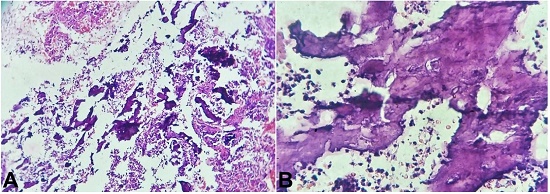

The histopathology of the endometrial biopsy showed an endometrium with bony remnants (Figure 2A). The bony remnants showed mature degenerated osteocytes, bone tissue, and calcification (Figure 2B).

The endometrial stroma showed a florid chronic inflammation predominantly composed of plasma cells and a few lymphocytes. Therefore, the report of chronic endometritis with osseous metaplasia was rendered. After a few days, we received the same patient’s hysterectomy specimen, which showed intrauterine bones in the endometrial cavity (Figure 3).